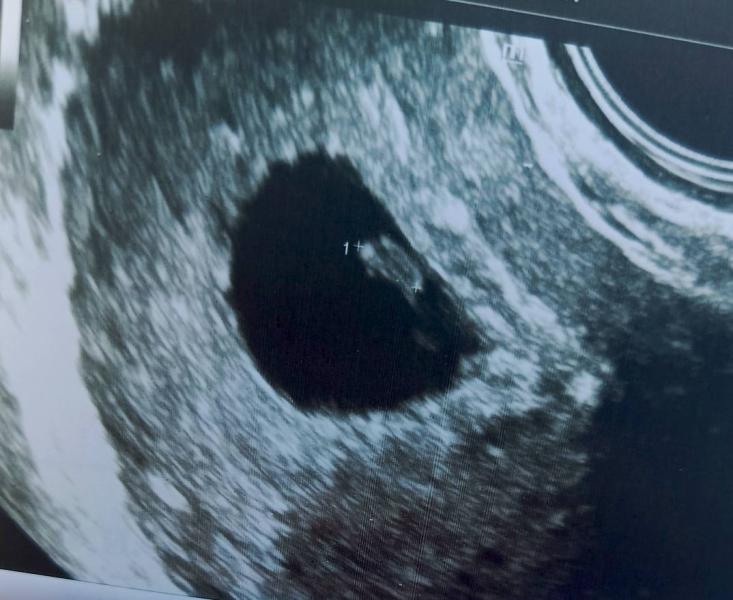

Сердечко бьется 😍126у/минуту. 4.4мм эмбриончик